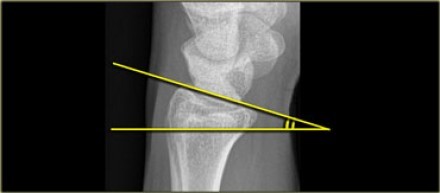

A

• Radial tilt is measured on a lateral radiograph.

• The radial tilt represents the angle between a line along the distal radial articular surface and the line perpendicular to the longitudinal axis of the radius at the joint margin.

• The normal volar tilt averages 11degrees (2 - 20 degrees)